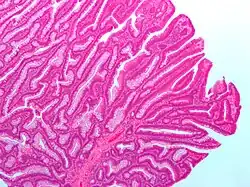

| Villous adenoma | 15%[16] to 40%[15] | Over 75% villous[14] | .jpg)

The common adenomas of the colon (colorectal adenoma) are the tubular, tubulovillous, villous, and sessile serrated (SSA).[18] A large majority (65–80%) are of the benign tubular type with 10–25% being tubulovillous, and villous being the most rare at 5–10%.[9]

The villous subdivision is associated with the highest malignant potential because they generally have the largest surface area. (This is because the villi are projections into the lumen and hence have a bigger surface area.) However, villous adenomas are no more likely than tubular or tubulovillous adenomas to become cancerous if their sizes are all the same.[18]

- Villous adenoma: 40% risk of cancer

Micrograph of a villous adenoma. These polyps are considered to have a high risk of malignant transformation. H&E stain.

Micrograph of a villous adenoma. These polyps are considered to have a high risk of malignant transformation. H&E stain. -